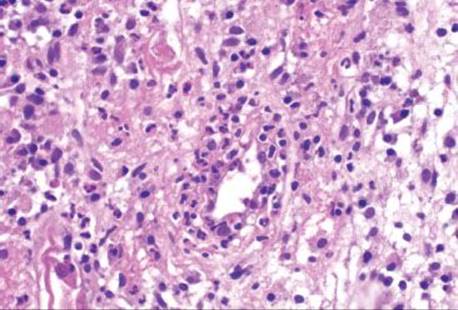

Decreased blood flow and lack of oxygen to the GI tract result in necrosis or tissue damage, causing ischemia. There are several weak points in the colonic blood supply, known as watershed areas, which result from incomplete anastomosis of the marginal arteries and lack of sufficient collateral circulation. These watershed areas are more vulnerable to ischemic injury than other parts of the colon and include the splenic flexure (or Griffith’s point), the rectosigmoid region at Sudeck’s point, and the ileocecal region. Among the older population, ischemic disease is typically attributable to atherosclerotic mesenteric vascular disease, but the causes of colonic ischemia are many (Table 4.2). The histologic findings are dependent on the timing of the ischemic event (Figs. 4.52–4.63). Early and minimal injury, for example, occurs first as degeneration and sloughing of superficial epithelial cells, edema, and vascular congestion. Later, the epithelial cells become markedly attenuated and the crypts appear compressed and atrophic (“microcrypts”) as the lamina propria swells and hemorrhages. Within 5 hours of total acute vascular occlusion, almost the entire intestinal wall appears necrotic. These changes are devoid of acute inflammation until reperfusion occurs. Paradoxically, reperfusion further injures the tissues by introducing oxygen free radical formation,16 the severity of which is dependent on the duration of the preceding hypoxia.